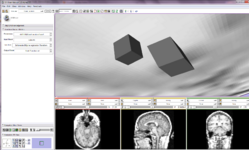

Home < Announcements:Slicer3.6Back to Documentation 3.6

The community of Slicer developers is proud to announce the release of Slicer 3.6.

- Slicer v3.6 - New and Improved Modules